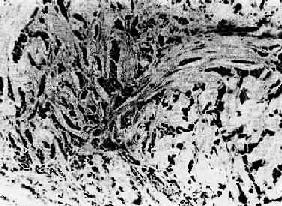

(3)实性癌(solid carcinoma):或称单纯癌(carcinoma simplex),属低分化的腺癌,恶性程度较高,多发生于乳腺,少数可发生于胃及甲状腺。癌巢为实体性,无腺腔样结构,癌细胞异型性高,核分裂像多见。有的癌巢小而少,间质结缔组织多,质地硬,称为硬癌(scirrhous carcinoma)(图7-14)。有的则癌巢较大较多,间质结缔组织相对较少,质地如脑髓,称为髓样癌(medullary carcinoma)。

图7-14 乳腺硬癌

癌细胞呈条索状排列,间质丰富,由多量纤维组织构成